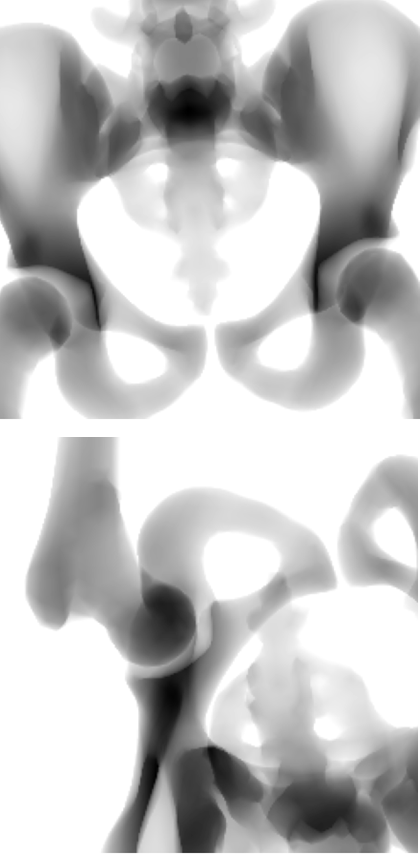

The SSM is registered to each patient from the dataset. This resulted in a base score with an average Hausdorff distance of 17.79\tsmm and a mean landmark error of 11.81\tsmm. The rotation and translation parameters obtained are assumed as the ground truth irrespective of the shape parameters. The 2D-3D reconstruction is tested by applying a random translation in the range of [-10,10]\tsmm and a rotation in the range of [-5,5] on all three axes for the SSM. The randomization is small due to the nature of the loss function being sensitive to changes only around a small region, such precision of initialization could be either provided manually or achieved with a network learning those initialization parameters. Fig. 3 shows sample outputs of our proposed method along with the quantitative results in Table 1. For evaluation, we consider only the images where the region of pelvis visible is greater than 50%percent5050\%.

Figure 3: Samples for 3D reconstruction from 2D projection images. (a) Target image, (b) Projection image with a random translation and rotation, (c) Projection image after registration, (d) Initial 3D overlay of template mesh, (e) 3D overlay of the meshes after registration, (f) NGC map after registration.